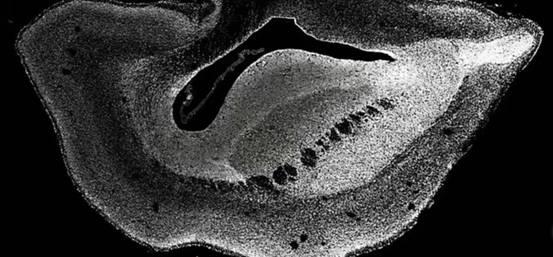

于是,为了证明自己的这一次猜想,科学家们进行了一个非常大胆的实验——将DNA片段“ARHGAP11B”,移植到了狨猴的胚胎之中。

实验结果令人惊讶,在植入了DNA片段“ARHGAP11B”之后,培育出的7个狨猴胚胎,大脑竟然开始了飞速发育,而且从发育的情况来看,开始出现了很多和人类一样的大闹特征——脑容积不断变大,同时表皮层出现了褶皱结构,显然,这意味着拥有DNA片段“ARHGAP11B”之后,实验的狨猴都开始变得更为聪明。

当然,最终处于安全的角度考虑,这7个狨猴胚胎并没有成功诞生,在获得了想要的实验数据之后,科学家们就停止了它们的发育。